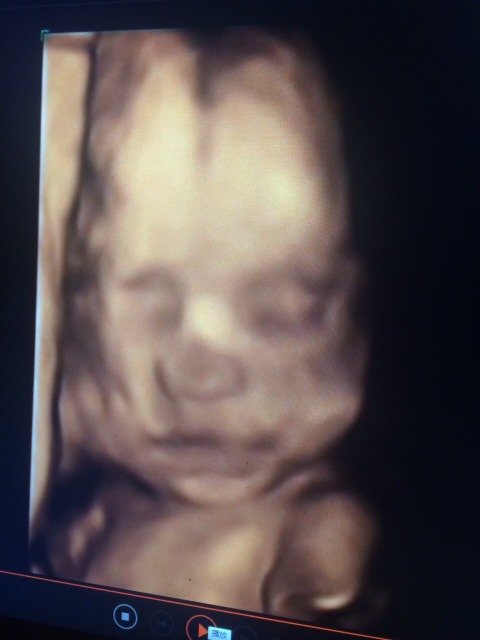

我宝宝的四维照,我老妈不懂这些,发过去把我老妈吓了一跳,还说宝宝是不是有问题,鼻子像猪八戒的鼻子,晕死,我觉得鼻子也不太好看怎么回事呀,我的鼻子很好看,老公的鼻头虽然有点大,整体还是不丑的,宝宝的咋会这样

你的宝宝的四维照显示是正常的,你的宝宝受遗传的基因也不会有你们两个不舒心的面孔的

还没发育好,看起来肯定有点奇怪